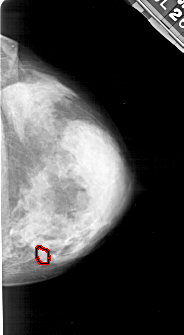

A_1185_1.RIGHT_CC

RIGHT_CC LINES 5011 PIXELS_PER_LINE 2746 BITS_PER_PIXEL 12 RESOLUTION 43.5 OVERLAY

FILE: A_1185_1.RIGHT_CC.OVERLAY

TOTAL_ABNORMALITIES 1

ABNORMALITY 1

LESION_TYPE CALCIFICATION TYPE PLEOMORPHIC DISTRIBUTION CLUSTERED

ASSESSMENT 4

SUBTLETY 3

PATHOLOGY MALIGNANT

TOTAL_OUTLINES 1

BOUNDARY